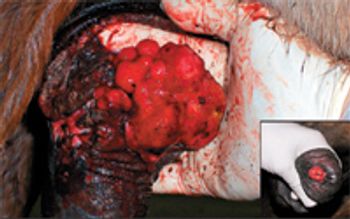

A horse's skin and coat can be contaminated via air and soil by various fungal organisms. Though also found on normal horses, some of these fungal organisms can produce significant fungal infection under the proper conditions. From the commonly recognized ringworm to the more insidious pythiosis, horses can be infected by these potentially nasty fungal infections, which are not only irritating, but also in the case of pythiosis, can be life-threatening.